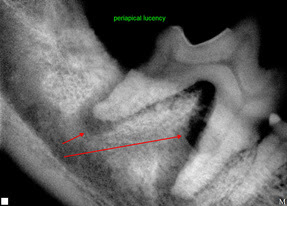

Small Animal Imaging

Sometimes, it requires a look inside to find what is troubling your pet. We have high-quality digital radiography (x-ray) capability, so we can see a tooth abscess that is under the gums, or a broken bone in the foot, or the engagement ring your dog swallowed.